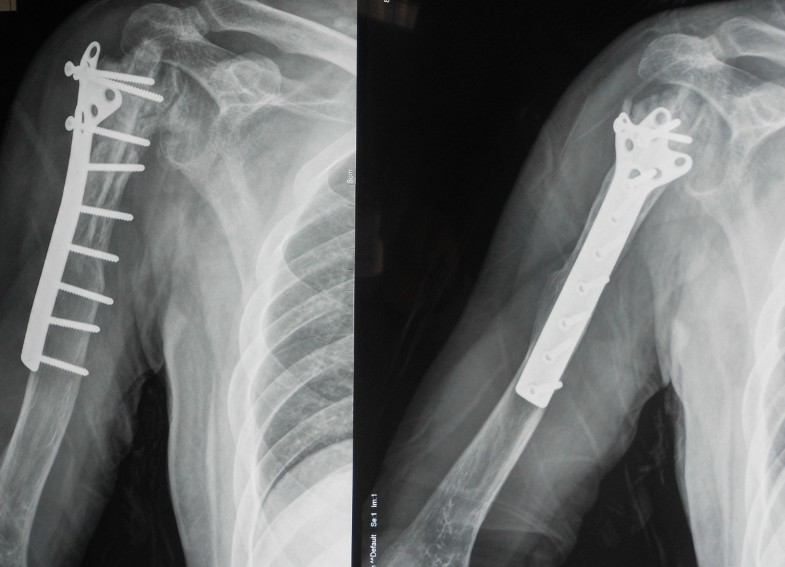

Treatment and of malignant bone tumors of the proximal humerus Pain In Humerus After Breast Cancer However, it turns out that shoulder pain, stiffness, or. The main symptoms of breast cancer that has spread to bone are: Symptoms when breast cancer has spread to the bones. For patients with breast cancer specifically, pain can arise in a variety of ways including symptomatic pain and pain related to cancer therapy. At first glance, shoulders seem distant from. Pain In Humerus After Breast Cancer.